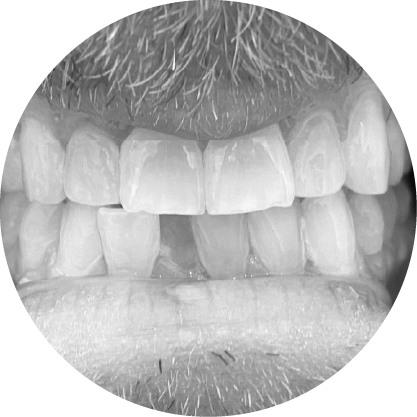

"ช่องว่างระหว่างฟันหรือไดแอสเทมา หมายถึงช่องว่างระหว่างฟันที่เห็นได้ชัด ซึ่งอาจเป็นปัญหาทางความงามสำหรับหลายๆ คนการจัดฟันสามารถปิดช่องว่าง เหล่านี้ได้อย่างมีประสิทธิภาพทำให้มีรอยยิ้มที่สม่ำเสมอและสวยงาม"

ตัวอย่างในชีวิตจริง